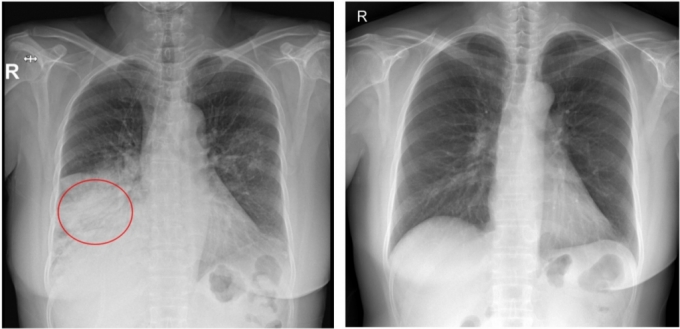

Áßȱǿ¡¼ Å« »ç¶ûÀ» ¹Þ¾Ò´ø ¹è¿ìÀÌÀÚ °¡¼ö ±¸ÁØ¿±ÀÇ ¾Æ³» °í(ͺ)¼Èñ¿øÀÇ »ç¸Á ¿øÀÎÀÌ ÃÖ±Ù ´Ù½Ã ÁÖ¸ñ¹Þ´Â´Ù. ¼Èñ¿øÀº ¾à 1³â Àü µ¶°¨À» ¾Î´Ù°¡ Æó·ÅÀ¸·Î »ç¸ÁÇÑ °ÍÀ¸·Î ¾Ë·ÁÁ³´Ù. ±âÀúÁúȯÀ» ¾Î´ø »óÅ¿¡¼ Æó·ÅÀÌ ¹ß»ýÇØ ÁúȯÀÌ ´õ Ä¡¸íÀûÀ¸·Î ÁøÇàÇßÀ» °¡´É¼ºÀÌ Á¦±âµÆ´Ù. Àü¹®°¡µéÀº °í·ÉÃþ°ú ±âÀúÁúȯÀÚÀÇ °æ¿ì Æó·Å À§ÇèÀÌ Å©°Ô ³ô¾ÆÁö´Â ¸¸Å, ¿¹¹æÁ¢Á¾À» Æ÷ÇÔÇÑ »çÀü °ü¸®°¡ ÇʼöÀûÀ̶ó°í °Á¶ÇÑ´Ù.

Æó·ÅÀº 2024³â ±âÁØ ±¹³» »ç¸Á¿øÀÎ 3À§ÀÌÀÚ È£Èí°èÅë Áúȯ »ç¸Á¿øÀÎ 1À§¸¦ ±â·ÏÇÒ Á¤µµ·Î Ä¡¸íÀûÀÎ ÁúȯÀÌ´Ù. ƯÈ÷ ±¹³» Æó·Å ȯÀÚ´Â 2021³â 51¸¸ ¸í¿¡¼ 2024³â 188¸¸¸íÀ¸·Î ¾à 3.7¹è Áõ°¡ÇÏ¸ç ºü¸£°Ô È®»êÇÏ´Â Ãß¼¼¸¦ º¸ÀδÙ.

Æó·ÅÀÇ ÁÖ¿ä ¹ßº´ ¿äÀÎÀº °í·É(65¼¼ ÀÌ»ó)°ú ¸¸¼º ½ÉÁúȯ, °£Áúȯ, ´ç´¢ µî°ú °°Àº ¸¸¼ºÁúȯÀÌ´Ù. ƯÈ÷ ±¹³»¿¡¼´Â ³ëÀΰú ±âÀúÁúȯÀÌ Àִ ȯÀÚÀÇ Áúº´ ºÎ´ãÀÌ »ó´ëÀûÀ¸·Î ³ô°í, »ç¸Á·ü°úµµ »ó´çÇÑ °ü°è°¡ ÀÖ´Â °ÍÀ¸·Î ³ªÅ¸³µ´Ù.

2006~2010³â ÀǷẸÇè û±¸ ÀڷḦ Ȱ¿ëÇÑ ÈÄÇâÀû ÄÚȣƮ ¿¬±¸¿¡ µû¸£¸é 50~64¼¼ ´ç´¢º´ ȯÀÚÀÇ Æó·Å±¸±Õ Æó·Å ¹ßº´ À§ÇèÀÌ °Ç°ÇÑ ¼ºÀκ¸´Ù ÃÖ´ë 3¹è, ¸¸¼º ½ÉÀåÁúȯÀÌ ÀÖÀ¸¸é 4.2¹è, ¸¸¼º ÆóÁúȯÀÌ ÀÖÀ¸¸é 9.8¹è±îÁö ³ô¾ÆÁö´Â °ÍÀ¸·Î È®ÀεƴÙ. ¶Ç ÀϺ»¿¡¼ 19¼¼ ÀÌ»ó ¼ºÀÎÀÇ ÀǷẸÇè û±¸ ÀڷḦ Ȱ¿ëÇÑ ¿¬±¸ °á°ú¿¡ µû¸£¸é ¾Ï ȯÀÚÀÇ Æó·Å ¹ßº´ À§ÇèÀÌ °Ç°ÇÑ ¼ºÀκ¸´Ù 12.5¹è ´õ ³ô¾Ò´Ù.

±âÀúÁúȯÀÚ´Â Æó·Å ¹ßº´ ½Ã »ç¸Á À§Çèµµ Å©°Ô ³ô¾ÆÁø´Ù. 2015³â Æ÷¸£Åõ°¥¿¡¼ Æó·ÅÀ¸·Î ÀÔ¿øÇÑ ¼ºÀΠȯÀÚ¸¦ ´ë»óÀ¸·Î ÇÑ ÈÄÇâÀû ºÐ¼® ¿¬±¸¸¦ ÁøÇàÇß´õ´Ï ¸¸¼º ½ÅÁúȯ, Æó¾Ï, ÀüÀ̼º ¾Ï, ¿îµ¿±â´É Àå¾Ö, Ä¡¸Å, ³úÇ÷°ü Áúȯ, ÇãÇ÷ ½ÉÁúȯ µîÀ» µ¿¹ÝÇÑ È¯ÀÚ´Â Æó·ÅÀ¸·Î »ç¸ÁÇÒ À§ÇèÀÌ ´õ ³ô¾Ò´Ù. µ¿¹Ý ÁúȯÀº À¯Çü¡¤¿øÀο¡ °ü°è¾øÀÌ, ÀÔ¿ø Áß Æó·ÅÀ¸·Î »ç¸ÁÇÒ À§ÇèÀ» °áÁ¤ÀûÀ¸·Î Áõ°¡½ÃŰ´Â ¿äÀÎÀ¸·Î ÀÛ¿ëÇÑ´Ù.

±èÀç¿ Á߾Ӵ뺴¿ø È£Èí±â¾Ë·¹¸£±â³»°ú ±³¼ö´Â "ÀÓ»ó ÇöÀå¿¡¼ ±âÀúÁúȯÀ» °¡Áø Æó·Å ȯÀÚÀÇ ¿¹ÈÄ´Â ±âÀúÁúȯÀÌ ¾øÀ» ¶§¿Í È®¿¬È÷ ´Ù¸£´Ù"¸ç "°Ç°ÇÑ »ç¶÷¿¡¼´Â °¨±âó·³ Áö³ª°¥ ¼ö ÀÖÁö¸¸, ½ÉÀ塤Æó¡¤ÄáÆÏ ±â´ÉÀÌ ¶³¾îÁø ȯÀÚÀÇ °æ¿ì, Æó·ÅÀ¸·Î ÀÎÇÑ Àü½Å ¿°Áõ ¹ÝÀÀ µîÀ¸·Î ±Þ°ÝÈ÷ ¾ÇÈÇÏ´Â °æ¿ì°¡ ¸¹´Ù"°í ¼³¸íÇß´Ù.